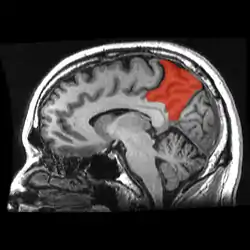

![]() Sagittal MRI slice with the precuneus shown in red. (Anterior to the left.) | |

Precuneus of left cerebral hemisphere (shown in red).